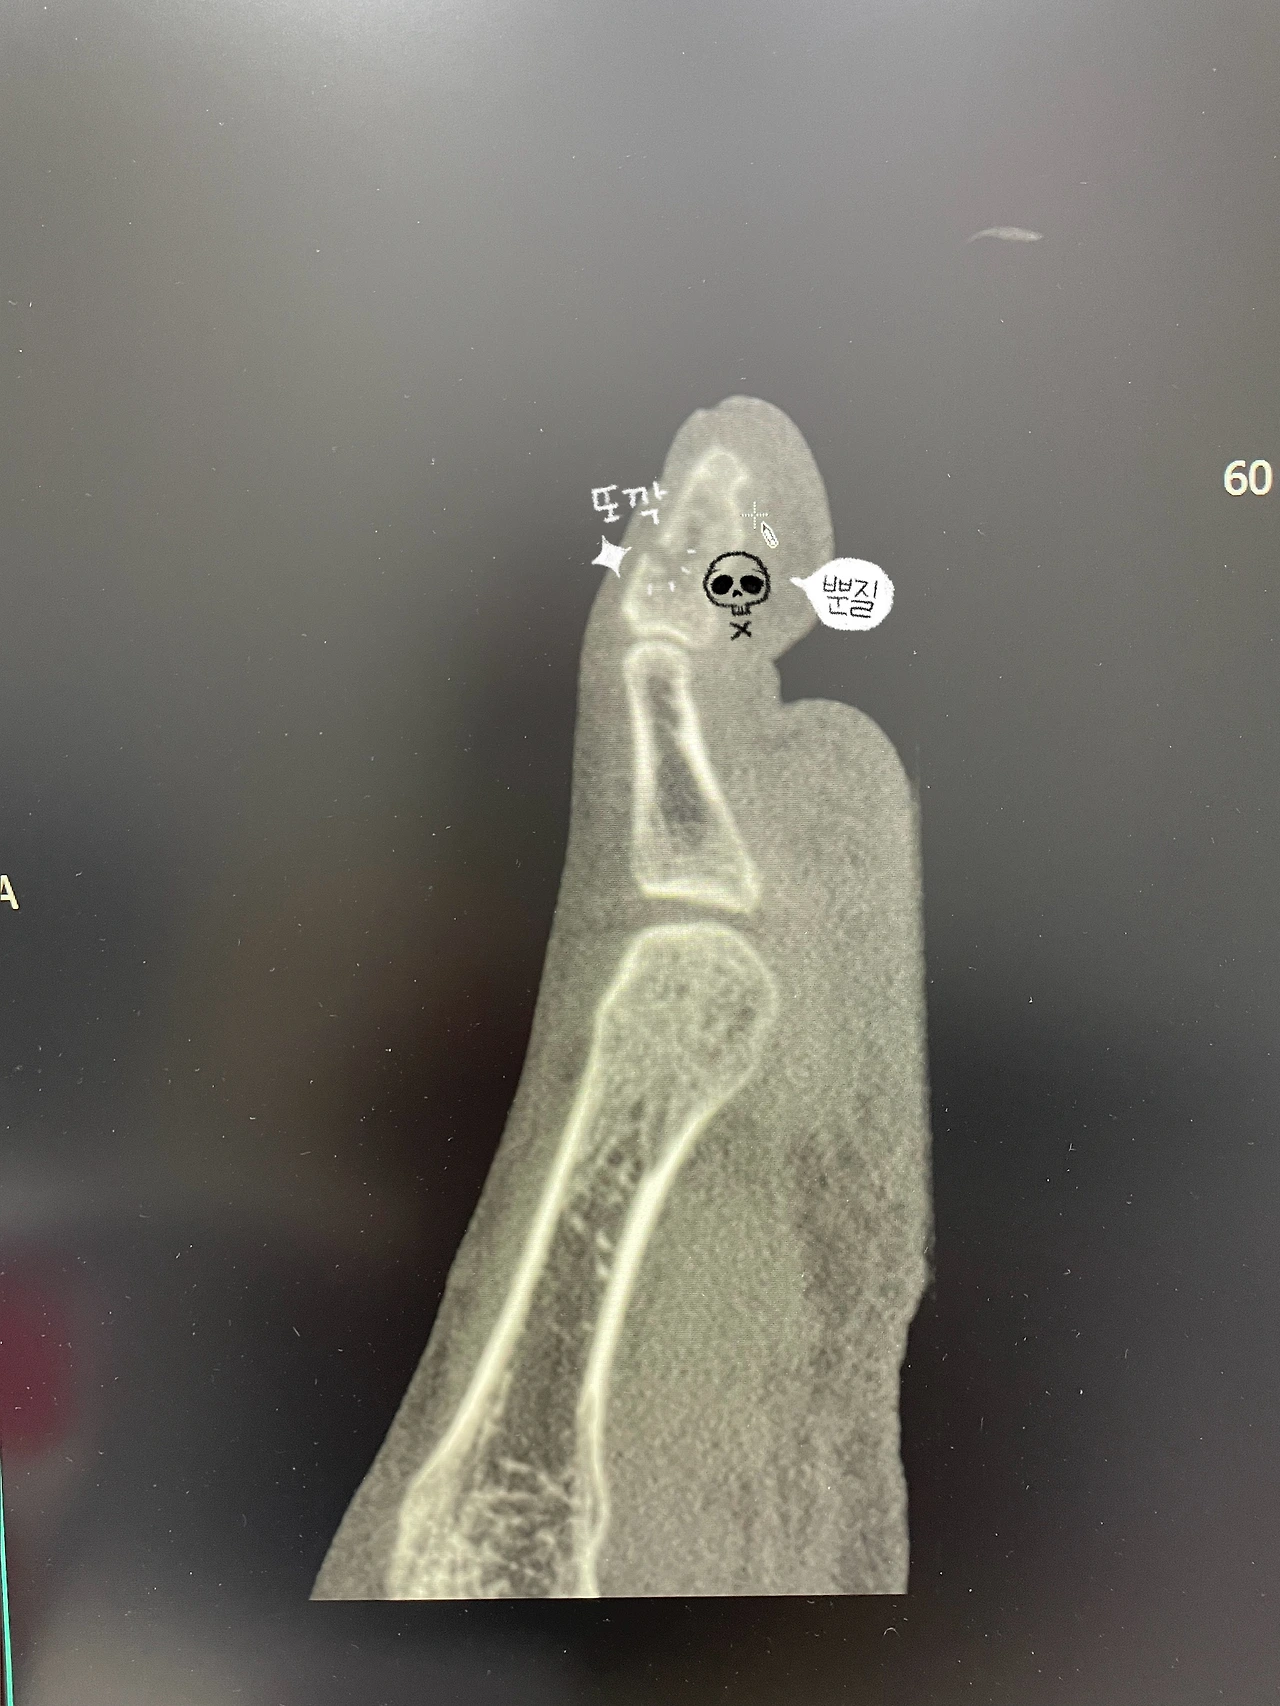

엑스레이 찍어보니 부러진거 확인,

발가락 전체가 부러진건지 확인하기 위해서 다시 CT를 찍었는데

완전한 골절 당첨.